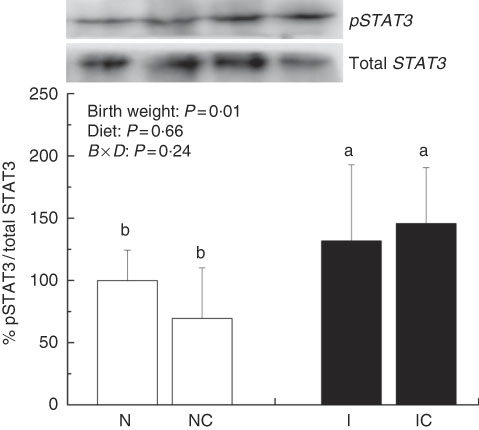

The IUGR rats exhibited higher (P<0·05) phosphorylated IκBα (Fig. 6) and nuclear phosphorylated NF-κB (Fig. 7) levels and lower (P<0·05) cytoplasmic phosphorylated NF-κB (Fig. 8) levels in the liver than in the NBW rats. In addition, the phosphorylated levels of JAK2 (Fig. 9) and STAT3 (Fig. 10) were higher (P=0·24, P=0·01) in the IUGR rats than in the NBW and NC groups. Dietary curcumin supplementation decreased the phosphorylated levels of IκBα (P<0·05) and JAK2 (P>0·05), and NF-κB (P>0·05) in the nucleus and cytoplasm of liver in the IC group.

Fig. 10 Abundance of phosphorylated signal transducer and activator of transcription 3 (STAT3) in liver of normal birth weight rats (N), normal birth weight (![]() ) rats supplemented with curcumin (NC), intra-uterine growth retardation (IUGR,

) rats supplemented with curcumin (NC), intra-uterine growth retardation (IUGR, ![]() ) rats (I) and IUGR rats supplemented with curcumin (IC) (12 weeks of age). B, birth weight; D, diet; B×D, interaction between the corresponding parameters. Results were corrected for total protein, n 6/group. a,b Mean values with unlike letters were significantly different when a significant interaction was observed (P<0·05).

) rats (I) and IUGR rats supplemented with curcumin (IC) (12 weeks of age). B, birth weight; D, diet; B×D, interaction between the corresponding parameters. Results were corrected for total protein, n 6/group. a,b Mean values with unlike letters were significantly different when a significant interaction was observed (P<0·05).

IUGR neonates are associated with a high risk of inflammation and oxidative stress( Reference Tarryadkins, Fernandeztwinn and Hargreaves 28 ). TNF-α is a key immune modulator, which can activate chemotactic cytokines and produce free radicals, leading to oxidative stress( Reference Starke, Daniel and Dumont 32 ). Furthermore, TNF-α, IL-1β and IL-6 have been implicated as prototype pro-inflammatory cytokines in the pathogenesis of sepsis( Reference Deventer 33 ). Higher TNF-α, IL-1β and IL-6 levels were observed in the serum of IUGR rats, which implied that pro-inflammation occurred in the body. Reports had demonstrated that a strong pro-inflammatory bias existed in IUGR with placental insufficiency( Reference Raghupathy, Al-Azemi and Azizieh 8 ). Significantly high concentrations of TNF-α, IL-1β and IL-6 in IUGR rats were significantly decreased after dietary curcumin supplementation, suggesting that curcumin could reduce inflammatory responses in the serum. These results are similar to those of previous studies in cells( Reference Liu, Shang and Li 34 ) and rats( Reference Soetikno, Sari and Veeraveedu 35 ). The liver is an important organ, and liver dysfunction has been observed in IUGR newborn pigs( Reference Junjun, Lixiang and Defa 7 ). The activities of AST and ALT are positively correlated with portal flow( Reference Kuo, Li and Alfrey 36 ). Hepatic ALT is usually located in the cytoplasm, whereas AST is distributed in the cytoplasm and mitochondrial fractions. However, when the structure of the liver is seriously damaged, ALT and AST are released into the circulatory system, resulting in the improvement of ALT and AST activity in the serum( Reference Nyblom, Berggren and Balldin 37 ). In this study, the activities of serum AST and ALT in the IUGR group were higher than those in the NBW group. The increased activities of serum ALT and AST are generally accepted biomarkers for hepatic dysfunction( Reference Tang, Chao and Xing 38 ). The vacuolisation and cell oedema from the histological examination of liver sections were prevalent in hepatocytes of IUGR rats, which revealed histological damage in the liver of IUGR rats. Meanwhile, fat cells also had mild denaturation. Similar to our findings, IUGR fetuses had a higher activity of glutamate oxaloacetate transaminase and impaired liver function than the normal ones( Reference Liu, Lin and Wang 39 ). After curcumin supplementation, the abnormal levels of serum AST and ALT and liver histological damage improved, and these results were not different from those observed in the normal condition. Previous studies had shown that curcumin could significantly reduce the levels of serum AST and ALT( Reference Zhao, Song and Chai 40 ) and liver injury in mice( Reference Zhang, Xu and Zhang 16 ) and rats( Reference Toydemir, Kanter and Erboga 22 ). Our findings indicated that diets supplemented with curcumin attenuated liver injury and inflammation in IUGR rats. Thus, we concluded that the protective effects of curcumin on the liver may be very important in IUGR rats. To investigate the immunomodulatory mechanisms of curcumin, we detected the expressions of the NF-κB and JAK/STAT pathways in the liver. NF-κB is found in cytoplasm bound to IκB. In response to various stimuli, including cytokines, stress and bacterial pathogens, the latent cytoplasmic NF-κB/IκB complex is activated by phosphorylation( Reference Hiscott, Kwon and Genin 41 ). Phosphorylation of IκB induces their ubiquitination, proteosome degradation and, subsequently, NF-κB release and nucleus translocation( Reference Echeverri, Nancy and Mockus 42 ). NF-κB is one of the most ubiquitous eukaryotic transcription factors that regulate the expression of genes associated with control of inflammatory responses, cellular proliferation/growth, cell adhesion and other processes( Reference Chen, Castranova and Shi 43 ). Our results showed that IUGR induced increased levels of phosphorylated IκBα and nuclear NF-κB and decreased levels of cytoplasmic phosphorylated NF-κB in the liver. Similar to our study, Zhong et al.( Reference Zhong, Li and Huang 44 ) also reported that the IκB was activated and the expression of NF-κB was increased by IUGR. These results suggested that the activation of the NF-κB/IκB complex might be related to increased levels of cytokines in IUGR, including TNF-α and IL-1β. The JAK2/STAT3 pathway is known to be involved in the immune response of numerous cytokines, including IL-6, and activated in response to injury( Reference Yang, He and Hao 45 ). Our results demonstrated that IUGR induced high levels of phosphorylated JAK2 and STAT3 in the liver. The activation of the JAK/STAT3 pathway might be the result of increased IL-6 in IUGR rats. Our results also showed that expression levels of Tnfa, Il1b and Il6 were up-regulated in the liver of IUGR rats. Importantly, dietary curcumin supplementation obviously inhibited the phosphorylation levels of the NF-κB pathway and JAK2 in IUGR rats and down-regulated the expression of those downstream genes. These observations supported that curcumin attenuated inflammation through the NF-κB( Reference Soetikno, Sari and Veeraveedu 35 , Reference Surh, Chun and Cha 46 ) and JAK/STAT pathways( Reference Kim, Park and Joe 47 ) in the liver of IUGR rats, which resulted in the negative regulation of cytokines (TNF-α) and pro-inflammatory interleukins (IL-1β and IL-6)( Reference Reyes-Gordillo, Segovia and Shibayama 48 ).